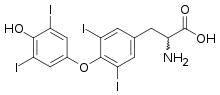

Amiodarone is structurally similar to thyroxine and also contains iodine. Both of these contribute to the effects of amiodarone on thyroid function.[28][29] Amiodarone also causes an anti-thyroid action, via Plummer and Wolff–Chaikoff effects, due its large amount of iodine in its molecule, which causes a particular "cardiac hypothyroidism" with bradycardia and arrhythmia.[30][31]

Amiodarone

Amiodarone Thyroxine

Thyroxine